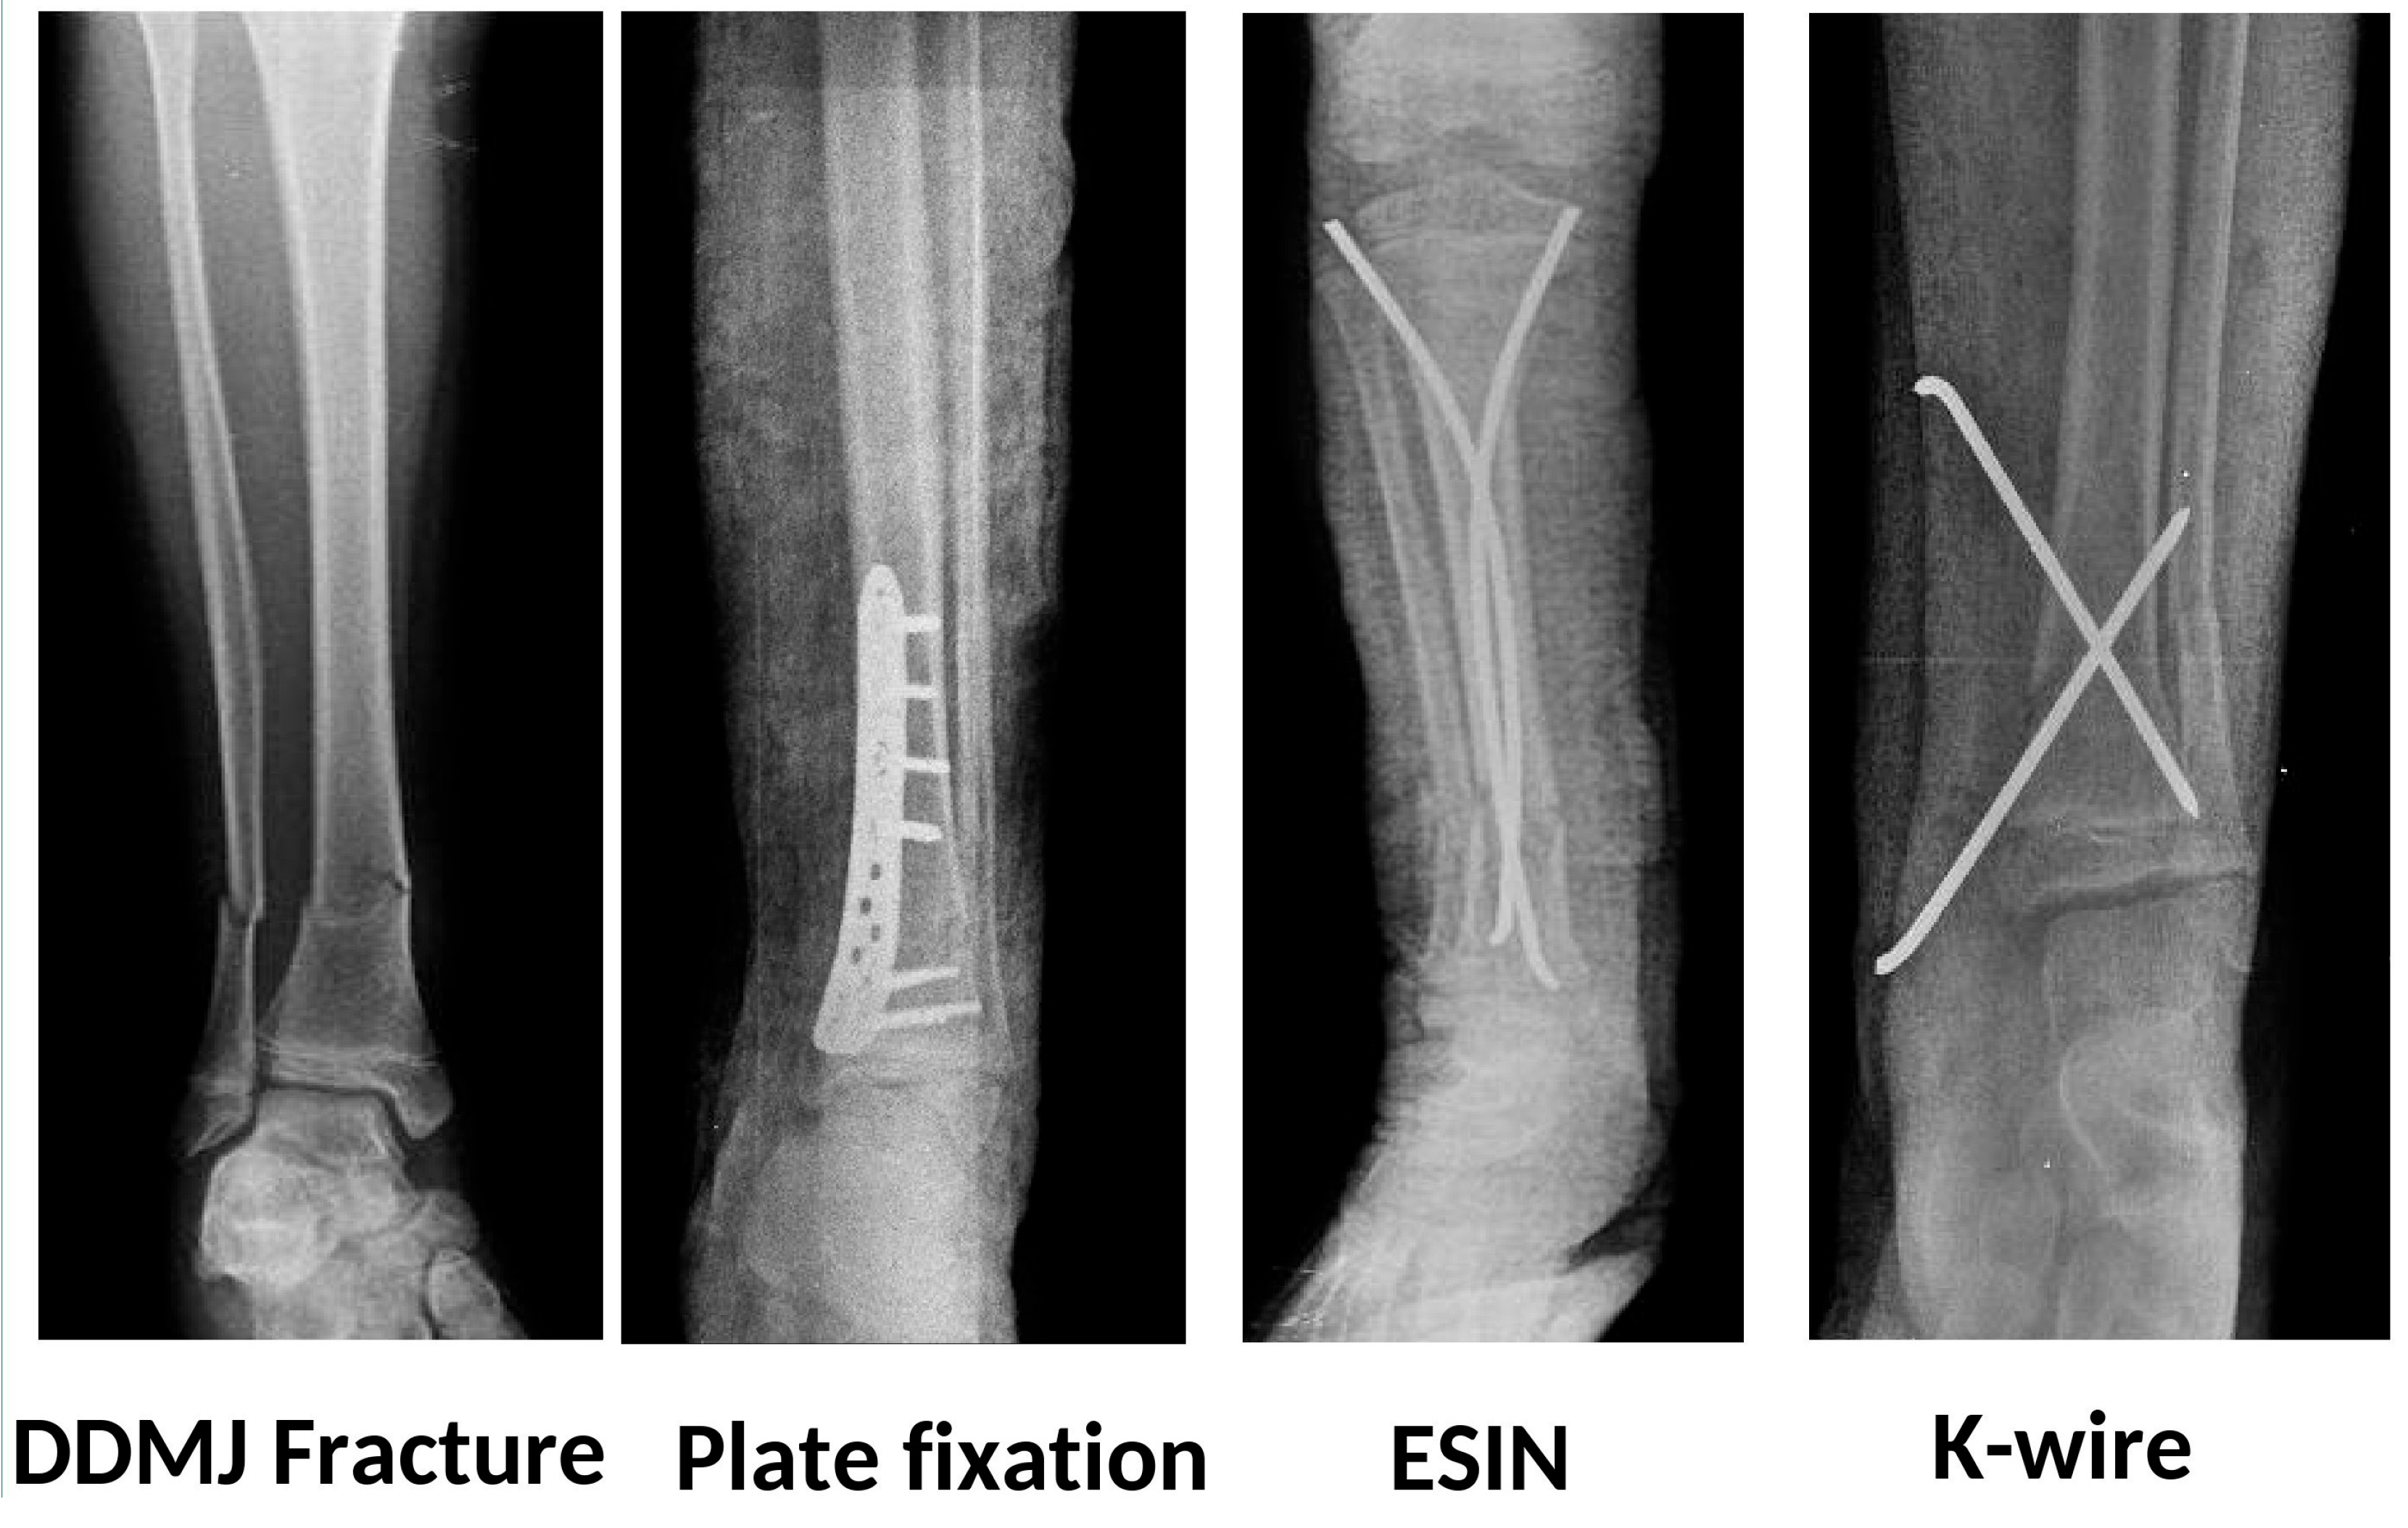

Patients were classified based on the fixation method: K-wire, plate, and ESIN (Figure 2). In the group treated with K-wire, if a fibular fracture was present, the fibula was fixed with a single retrograde K-wire. In the other two groups, no fixation was performed even if a fibula fracture was present. In the plate group, no extensive surgical dissection was performed, and minimal invasive plating techniques were followed. In the TEN group, fixation was achieved through antegrade insertion of two elastic nails, ranging in size from 2 to 4 mm depending on the morphology of the tibia.

Figure 2.

Radiographic images of patients who undergone plate fixation, ESIN, and K-wire fixation, respectively.